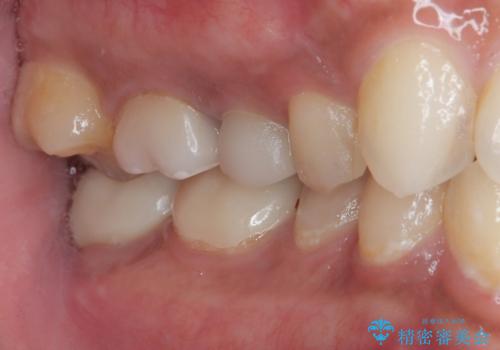

見た目、機能面ともに満足していただけました。

咬み合わせが強く以前のセラミックを割ってしまっているので就寝時にはナイトガードを使ってもらう予定です。

今後もメンテナンスで通っていただきながら、経過観察していく予定です。